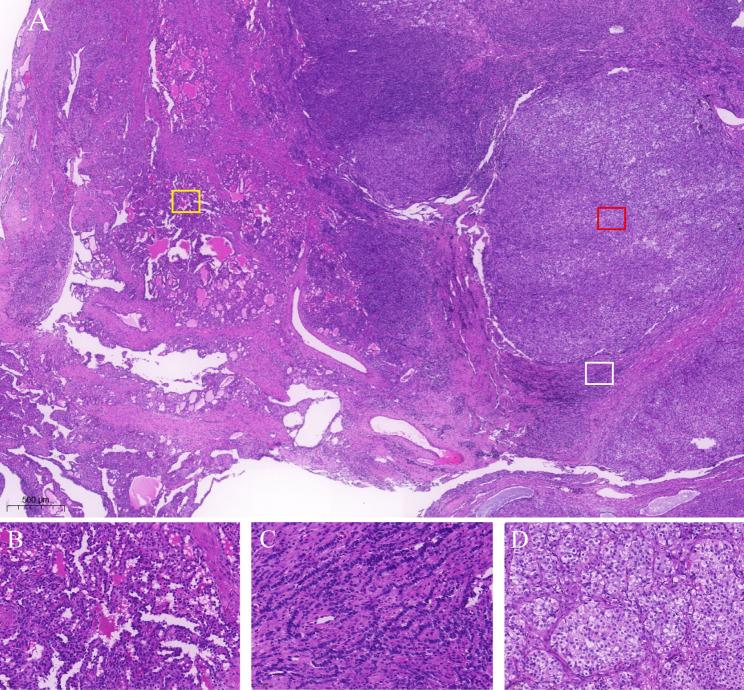

A 62-year-old postmenopausal woman presented with abdominal distension. Serum testosterone was elevated (4.43 nmol/L; normal range 0.45-1.26nmol/L). Ultrasound revealed a large multilocular cystic lesion with solid components in the pelvic-abdominal region, marked by abundant blood flow within the septa and solid areas, along with low-resistance arterial flow in the solid component of the tumor. CEUS demonstrated rapid and heterogeneous high enhancement in the tumor's cystic wall, septa, and solid components during the wash-in phase. Additionally, there was early washout compared to the myometrial layer. Total hysterectomy with bilateral salpingo-oophorectomy was performed. Histopathology confirmed moderately-poorly differentiated SLCT.

一名62岁绝经后女性出现腹胀。血清睾酮升高(4.43 nmol/L;正常范围0.45 - 1.26 nmol/L)。超声显示盆腔-腹部区域有一个大的多房囊性病变,伴有实性成分,其特征为分隔及实性区域内血流丰富,肿瘤实性成分呈低阻力动脉血流。CEUS显示在动脉期肿瘤的囊壁、分隔及实性成分呈快速且不均匀的高增强。此外,与肌层相比有早期廓清。行全子宫双侧附件切除术。组织病理学证实为中-低分化SLCT。